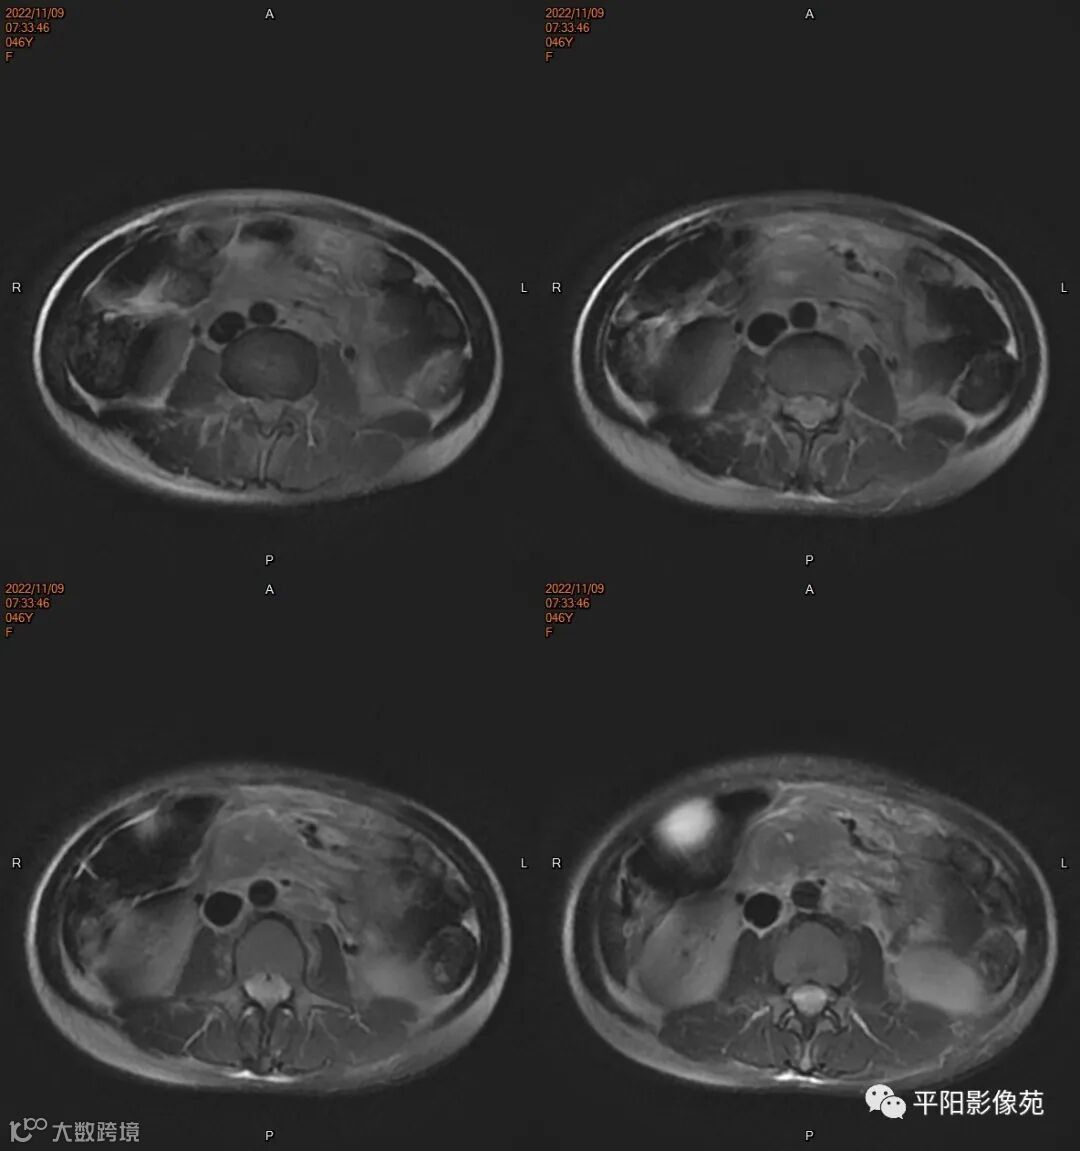

MR

影像表现: